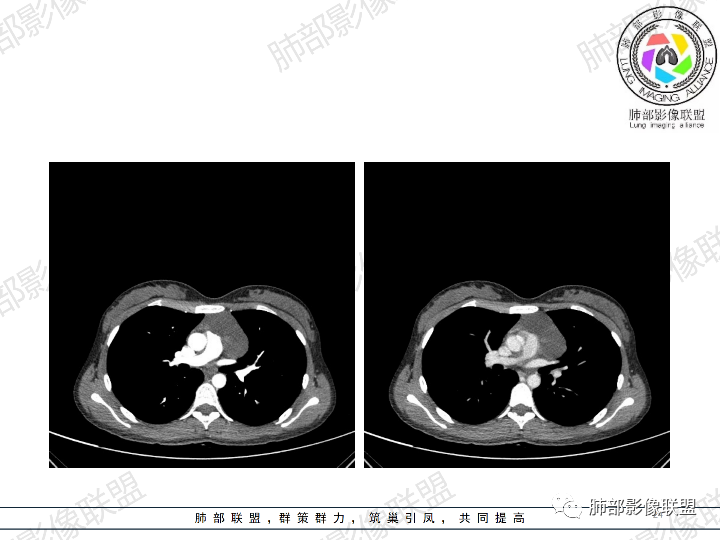

年轻女性,体检发现纵隔肿块。

影像:前纵隔一实性肿块,形态不规则,沿主动脉间隙生长,部分包绕大血管,边界欠清,周围脂肪间隙消失,平扫密度尚均匀,增强扫描大部分强化不明显,病灶左下部分似有高强化,强化病灶与血管分界清楚,考虑:1淋巴瘤(一般居中,病灶较软,包绕血管)

女性,23岁,体检发现纵隔占位。CT示前纵隔不规则占位,沿间隙生长,局部包绕大血管及心包,增强内部可见部分区域呈明显渐进性强化,其余部分强化不明显,考虑囊性畸胎瘤或神经鞘瘤>淋巴瘤,太年轻不考虑胸腺瘤

青年女性患者,体检发现左前纵隔占位性病变,胸部CT:左前纵隔见一不规则占位性病变,整体边界清楚,紧贴血管,间隙不明显,内部密度尚均匀,未见钙化及脂肪密度,增强扫描不均匀轻度强化,总体考虑偏良性病变,胸腺增生?

23岁女性

无症状

这个病灶有点怪

1、形态,似乎与常规肿瘤不一致

2、有间隔

3、密度强化有点怪

这些边缘收缩

符合胸腺正常形态

这是腺体内的一个囊性病变:

这是腺体内的另一个

南边:

倾向于:一个正常增大的腺体内的病变

根据部位:腺体首先考虑胸腺,其次才考虑异位结构

胸腺内囊、实性占位

首先支持胸腺增生并感染

其次胸腺瘤

然后才考虑异位的病变

这个病例的特点就是病灶整体符合胸腺的形态,如果它是肿瘤,它周围侵袭性不明确的话,它应该膨隆的挺厉害,它单纯就是一个膨隆性生长的,那么它就应该是类圆形的,边缘应该是膨大的,但是这个病例不是,有些地方边缘是收缩的,那么就是原有的胸腺基础上内部出了问题,里面强化增生明显就有可能是在原有胸腺基础上里面滋生出来一个病变。年龄确实年轻,又是女性。胸腺里面的病例多是胸腺瘤、胸腺癌、淋巴瘤。既然定的是胸腺里面的病变,那么就在这里面考虑。淋巴瘤首先不是。那么就是胸腺瘤和胸腺增生,胸腺囊肿的说法也有很多,因为胸腺增生里面有一种就是囊性的增生,里面有些地方有强化,囊肿合并感染了可以有,慢性炎性的肉芽肿的可以有强化。不能排除胸腺瘤,胸腺瘤放后面,一个原因就是太年轻了。如果考虑胸腺瘤,年龄不太符合,心里不踏实。我认为大家不考虑胸腺瘤是正常的思维,写报告也是待排,放第一诊断不合适。考虑有胸腺瘤是因为强化,占位效应,间隔。